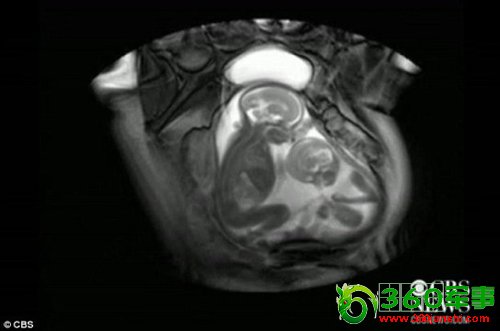

扫描发现双胞胎在子宫里“打架”(图)

核磁共振成像技术显示,一对双胞胎在妈妈肚子里拳脚相向“掐架”